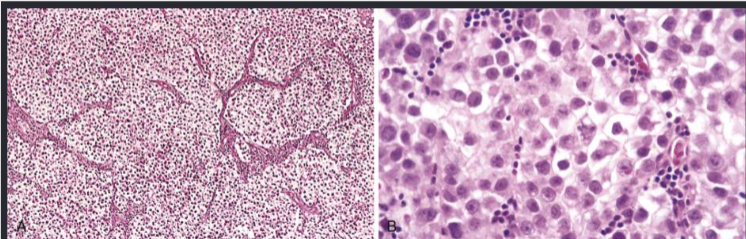

• Histopathology of SEMINOMA → Cells are large and round with distinct cell membrane, large central nucleus with prominent nucleo

yolk sac tumor

• Have Schiller-Duvall bodies (resemble primitive glomeruli)